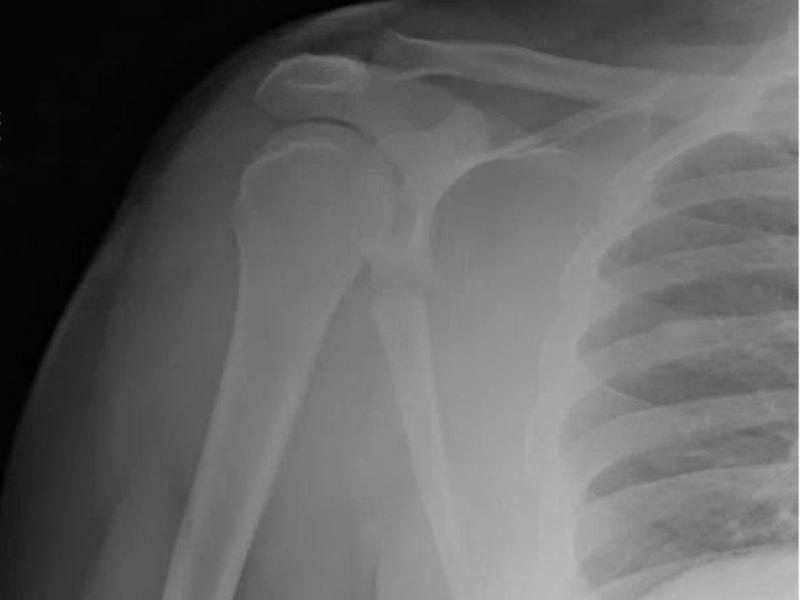

What's the diagnosis?  By Dr. Loran Hatch

A 35 yo male presents with right shoulder pain. He was